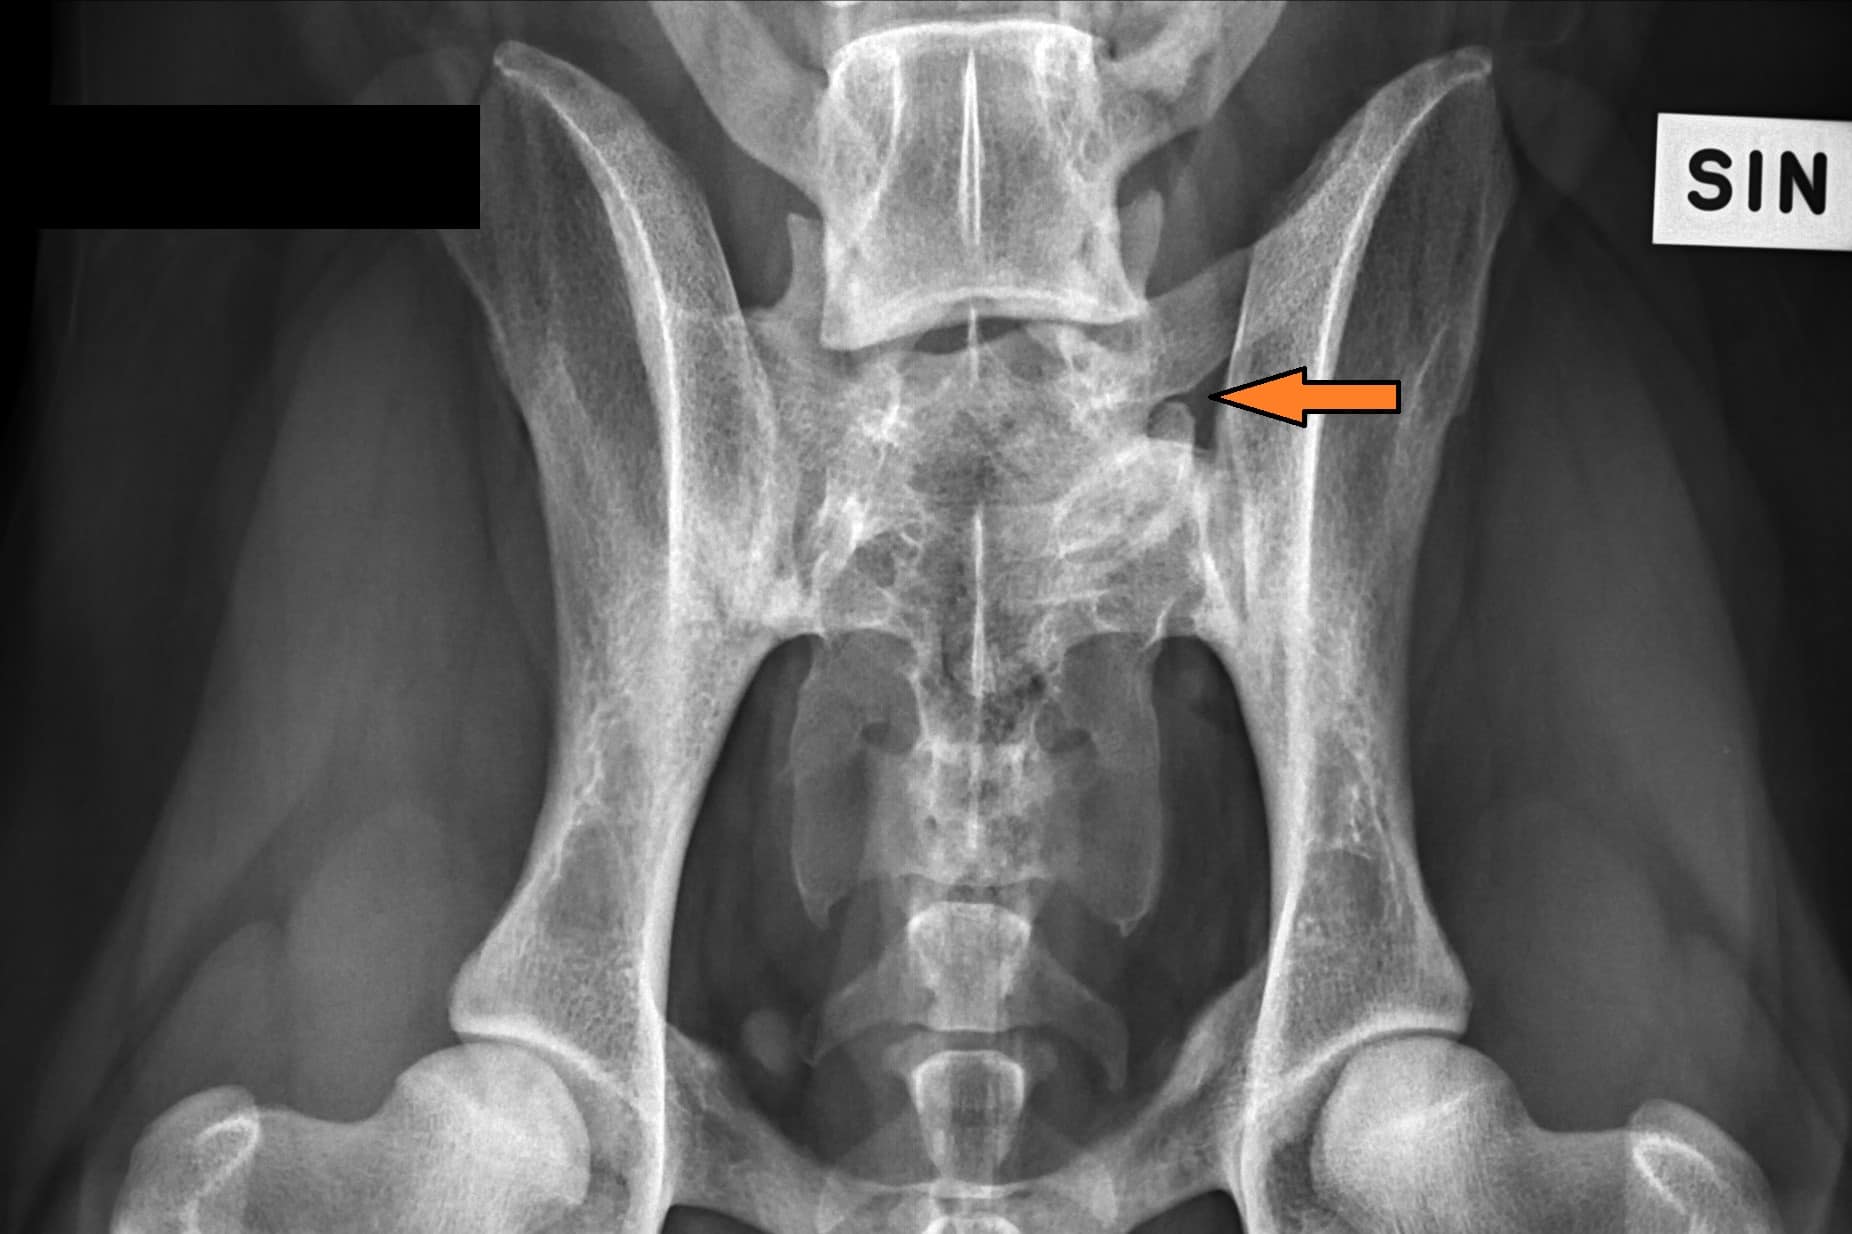

The first post is about lumbosacral transitional vertebra (LTV) in rhodesian ridgebacks.